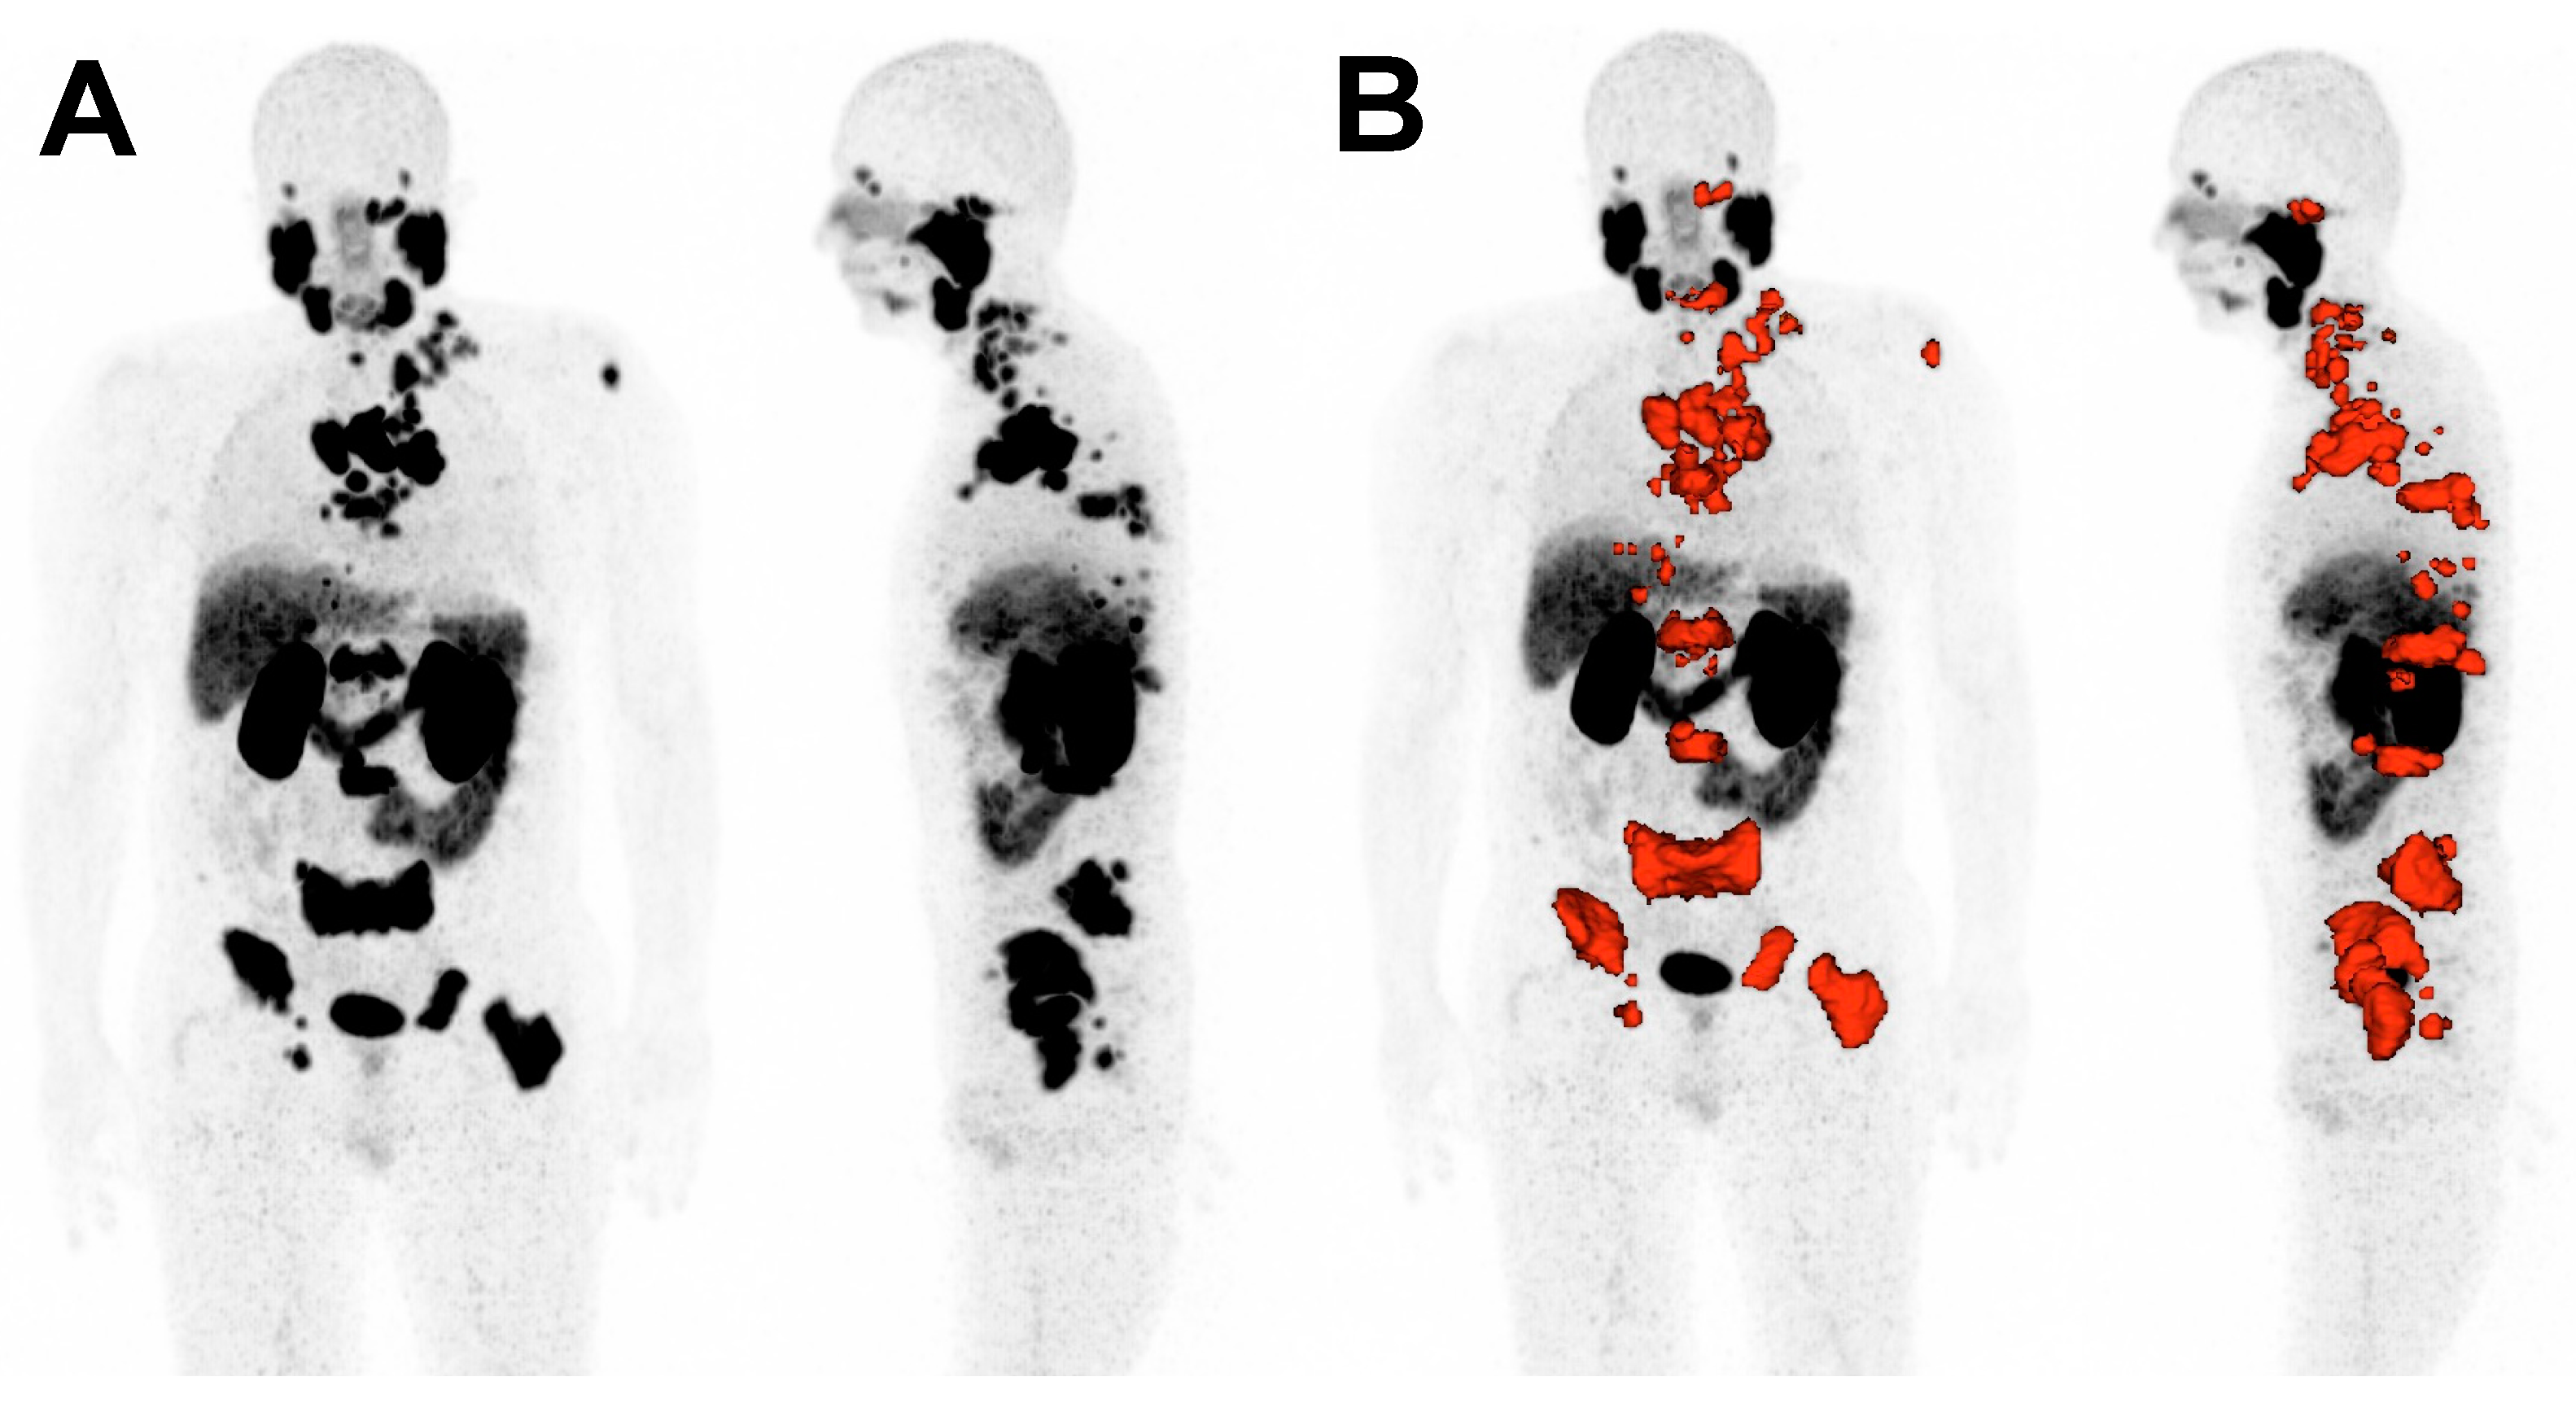

The imaging biomarkers to be analyzed included the maximum standardized uptake value of the tumor lesions (SUVmax), the mean standardized uptake value of all tumor lesions (SUVmean), the whole-body molecular tumor volume (MTV), and the whole-body total lesion PSMA (TLP), which is the analogue parameter to the established total lesion glycolysis (TLG) on [18F]FDG PET/CT [23,24]. TLP was defined as the summed products of volume and uptake (∑ Volume × SUVmean) of all lesions. MTV and TLP were calculated by a semi-automated tumor segmentation algorithm using Syngo.Via software (Enterprise VB 40B, Siemens, Erlangen, Germany). A standardized uptake of SUV ≥ 3 was used as a threshold for delineation of tumor lesions as described by Ferdinandus et al. [25]. Lesions that fell below a volume < 0.2 mL were excluded. Physiological uptake, e.g., in the bladder, spleen, liver or salivary glands, was manually excluded. Liver metastases were segmented by a threshold value of 1.5 × SUVmean of non-metastatic liver tissue. Figure 1 depicts exemplarily tumor segmentation using Syngo.Via software (VB 40B).

Figure 1. Representative example of tumor delineation using Syngo.Via software (VB 40B). (A): Maximum intensity projection (MIP) of [68Ga]Ga-PSMA-11 PET/CT. (B): Tumor tissue is delineated in red.